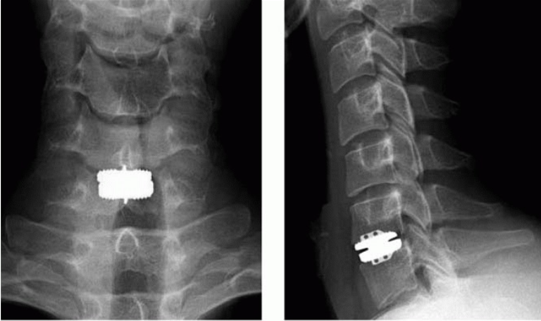

Front and Side X-Rays of Cervical Disk Replacement

X-rays taken from the front (Left) and side (Right), show a patient treated with cervical disk replacement for soft disk herniation.

Reproduced from Rhee J, Yoon T, Riew KD. Cervical Radiculopathy. J Am Acad Orthop Surg 2007;15(8):486-494.